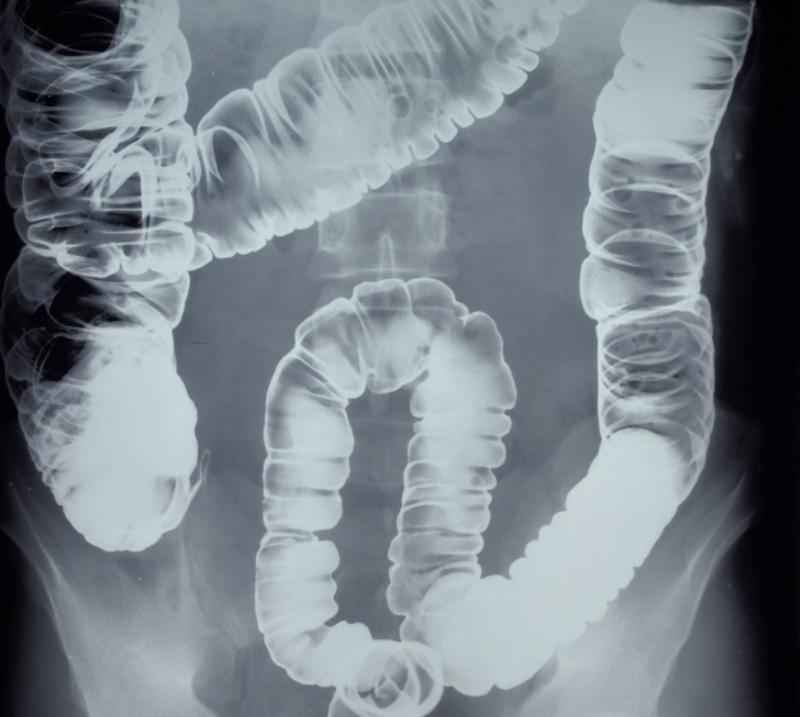

Chụp X-quang đại tràng: Đây là phương pháp sử dụng thuốc cản quang để chụp X-quang đại tràng. Thuốc cản quang sẽ giúp bác sĩ quan sát rõ hơn hình ảnh của đại tràng.

Chụp Xquang đại tràng